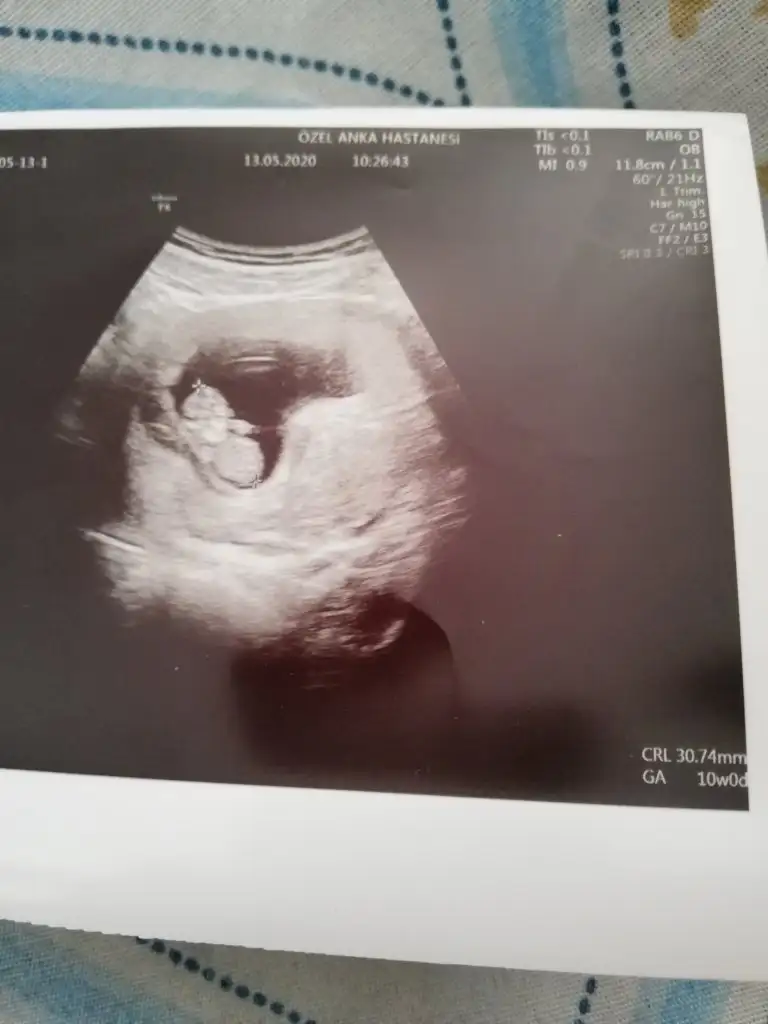

Benim ilk hamileliğim de 16. Haftama kadar doktor göstermedi deyip durmuştu ama ben erkek olduğunu 10. Haftamda anlamıştım kemik yapısından öyle de çıktı bildiğim şeyi doktor ancak 16. Haftada söyleyebildi

Kemik yapısından nasıl anlaşılıyor?

Eklentiler

• IMG_20200513_123238.webp

IMG_20200513_123238.webp

21,3 KB · Görüntüleme: 126